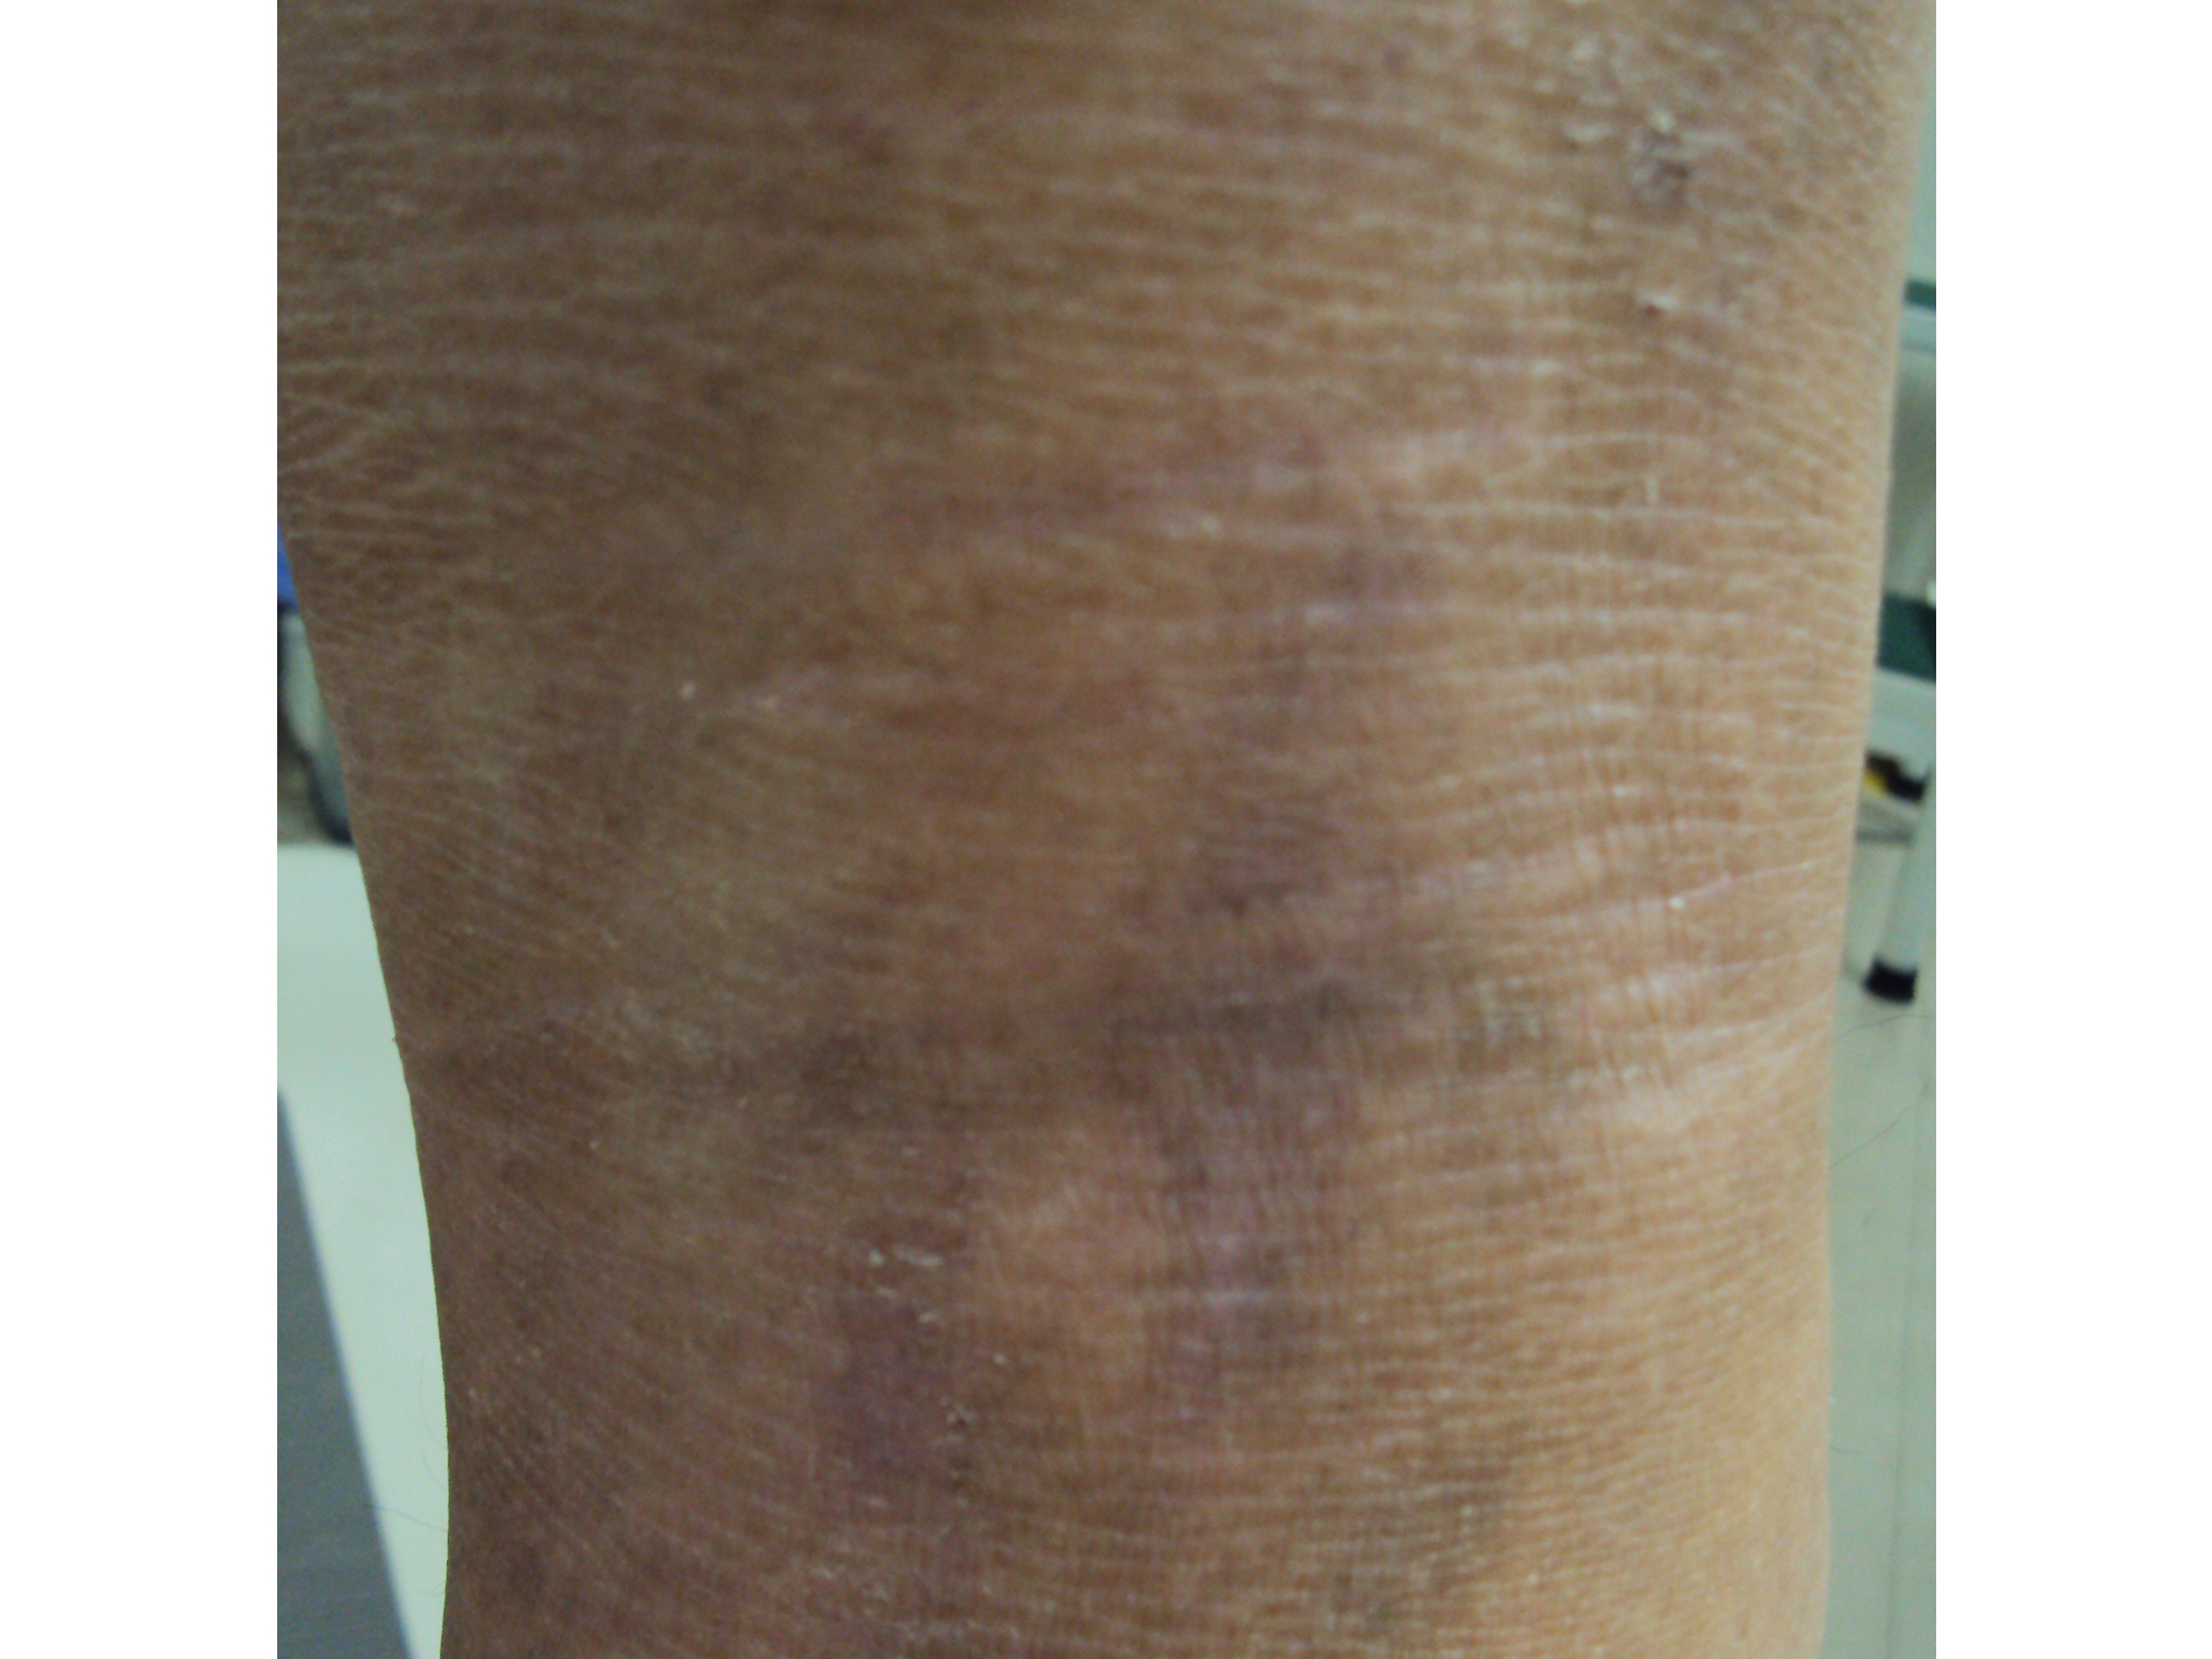

アトピー性皮膚炎

左膝裏

オゾン療法施行 前 オゾン療法施行 後